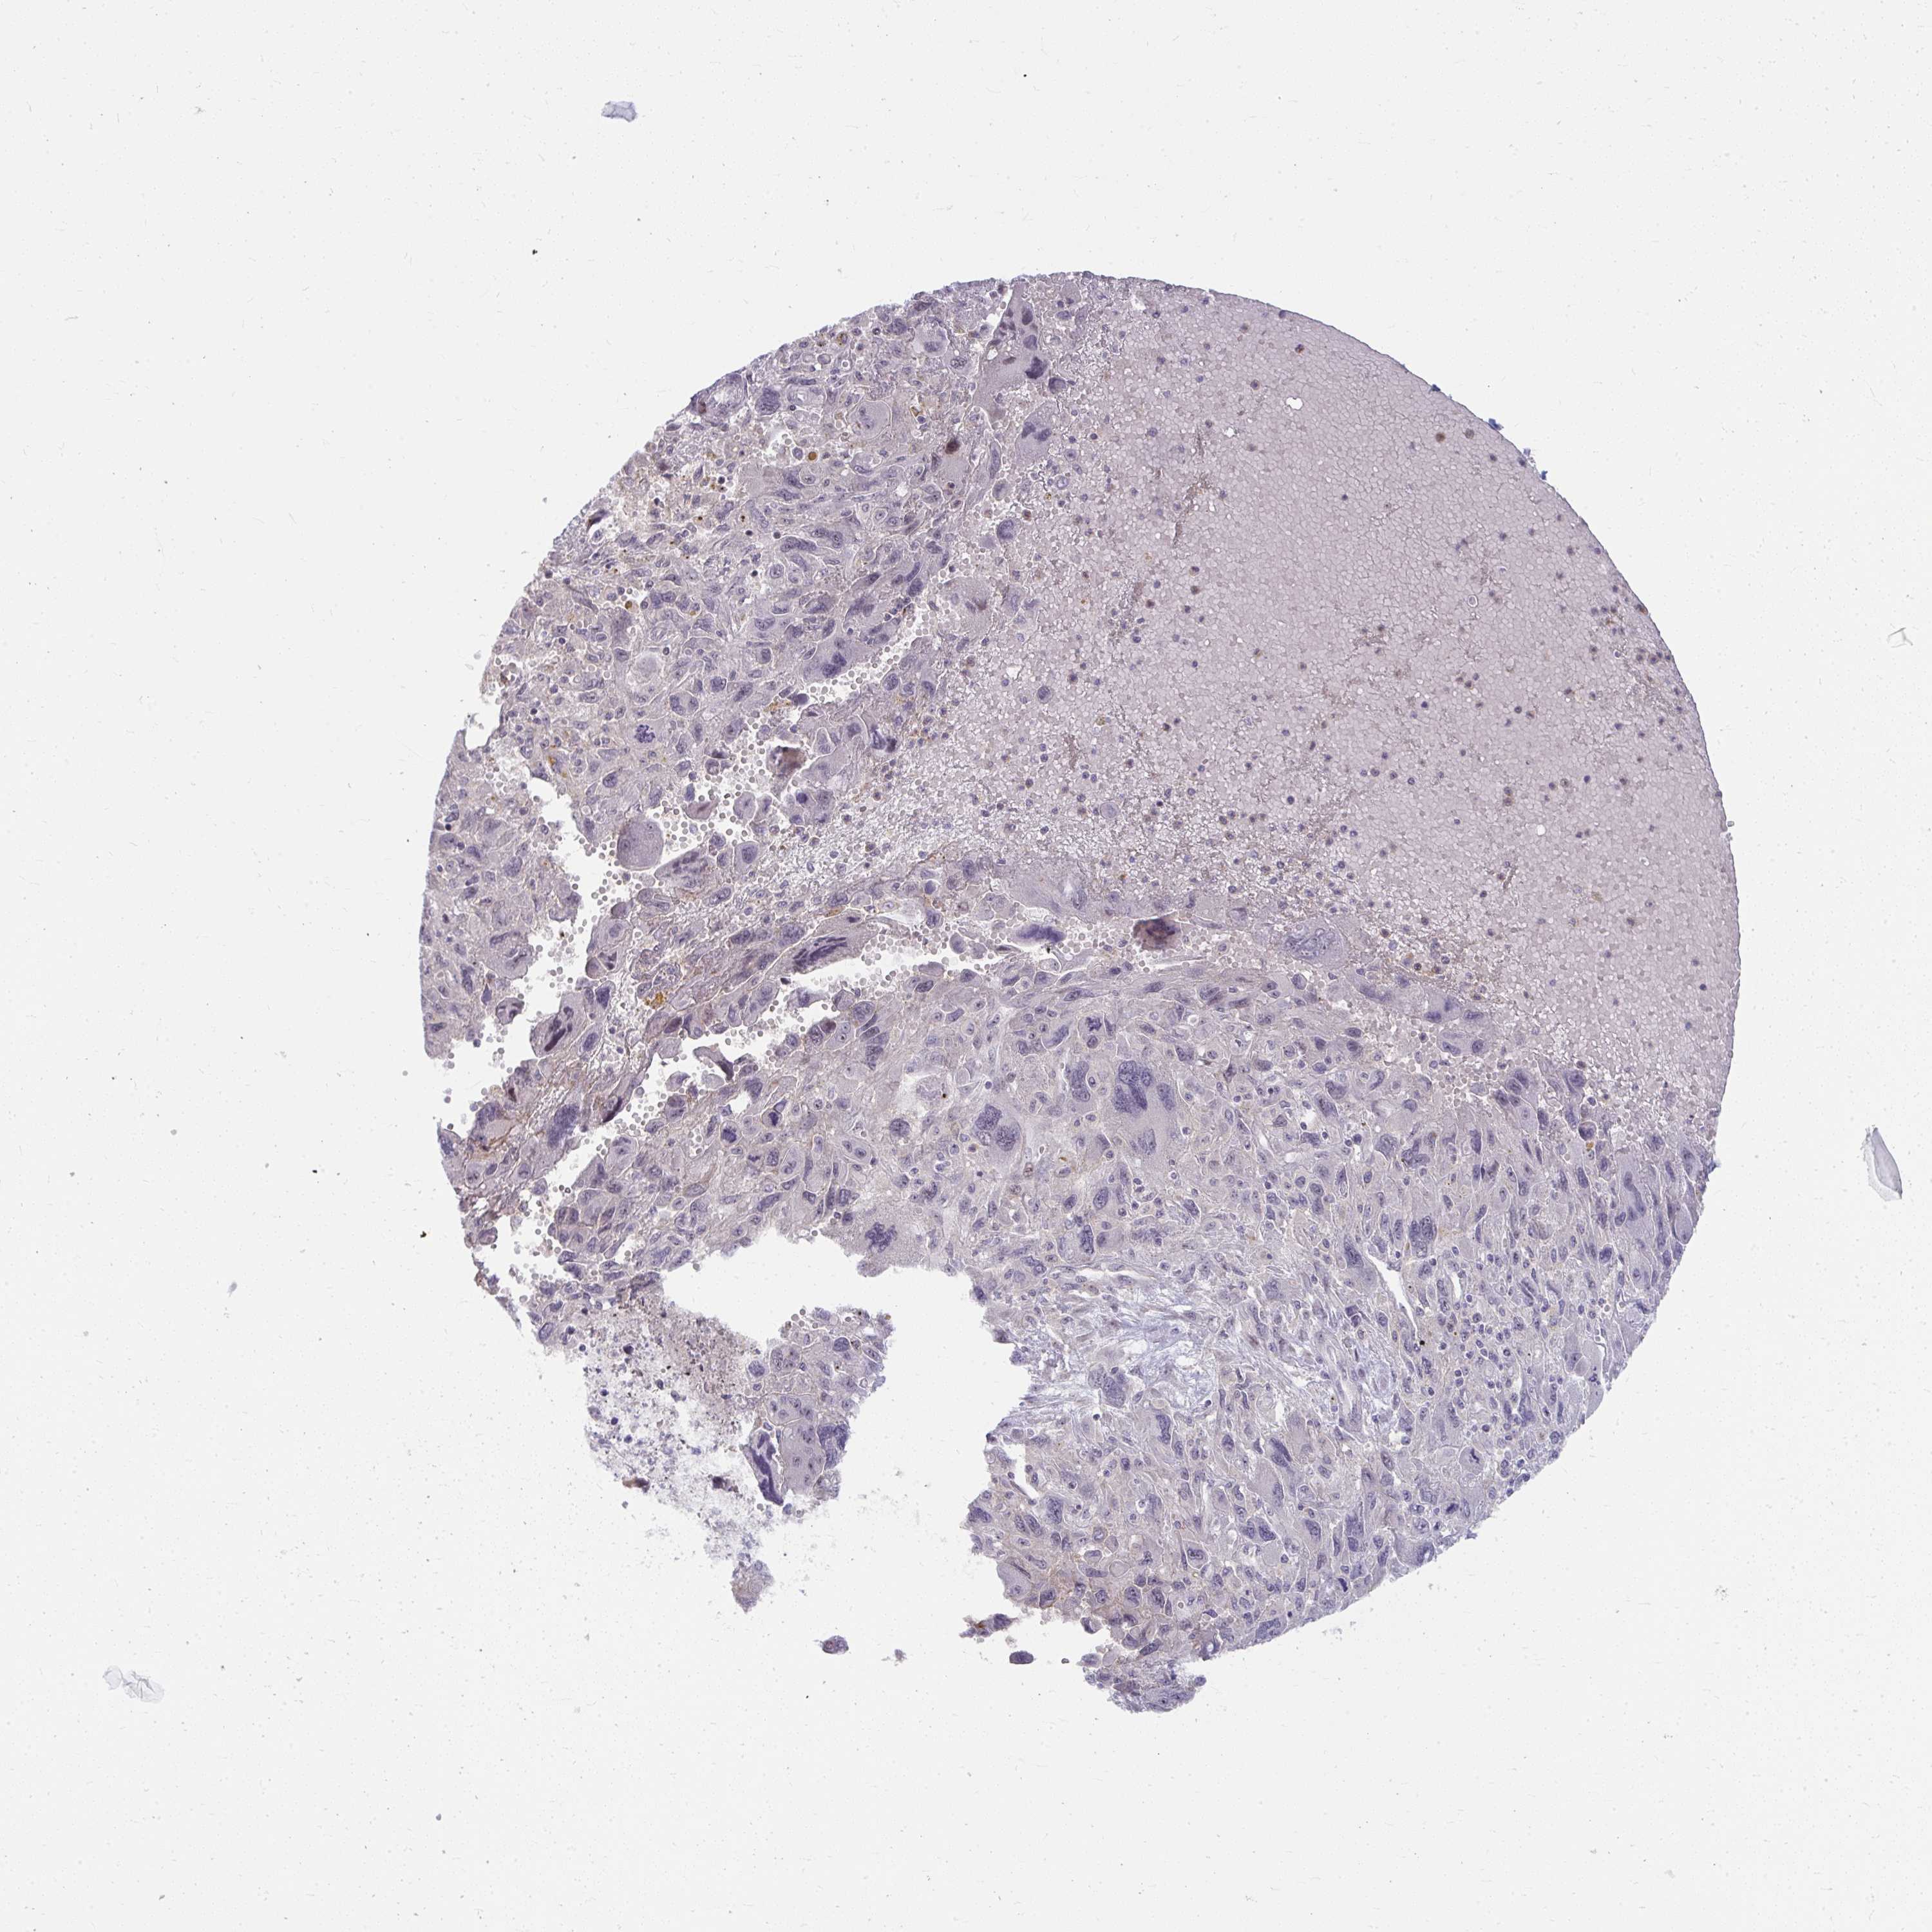

PANCREATIC CANCER - Protein expressioni

A mouse-over function shows sample information and annotation data. Click on an image to view it in a full screen mode. Samples can be filtered based on level of antibody staining by selecting one or several of the following categories: high, medium, low and not detected. The assay and annotation is described here.

Note that samples used for immunohistochemistry by the Human Protein Atlas do not correspond to samples in the TCGA dataset.

Antibody stainingi

Antibody staining in the annotated cell types in the current human tissue is reported as not detected, low, medium, or high, based on conventional immunohistochemistry profiling in selected tissues. This score is based on the combination of the staining intensity and fraction of stained cells.

Each image is clickable and will lead to virtual microscopy that enables deeper exploration of all samples and also displays staining intensity scores, fraction scores and subcellular localization as well as patient and tissue information for each sample.

Antibody HPA059530

Staining

High

Medium

Low

Not detected

Intensity

Strong

Moderate

Weak

Negative

Quantity

>75%

75%-25%

<25%

None

Location

Nuclear

Cytoplasmic/membranous

Cytoplasmic/membranous,nuclear

Adenocarcinoma, NOS